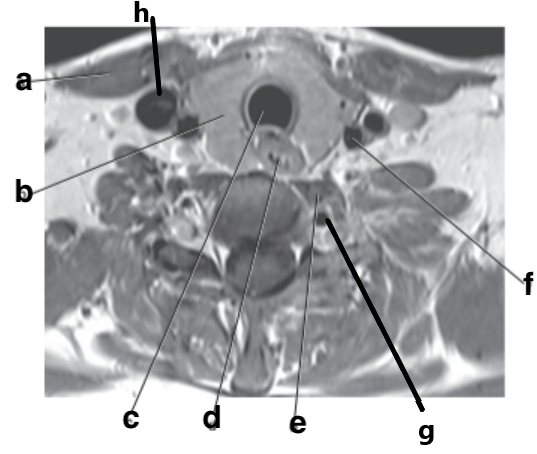

What is letter b?

Left ventricle

What is letter a?

Vertebral artery

Thyroid gland

Parotid gland

Trachea

Internal carotid artery

Submandibular gland

What is letter h?

What is letter c?